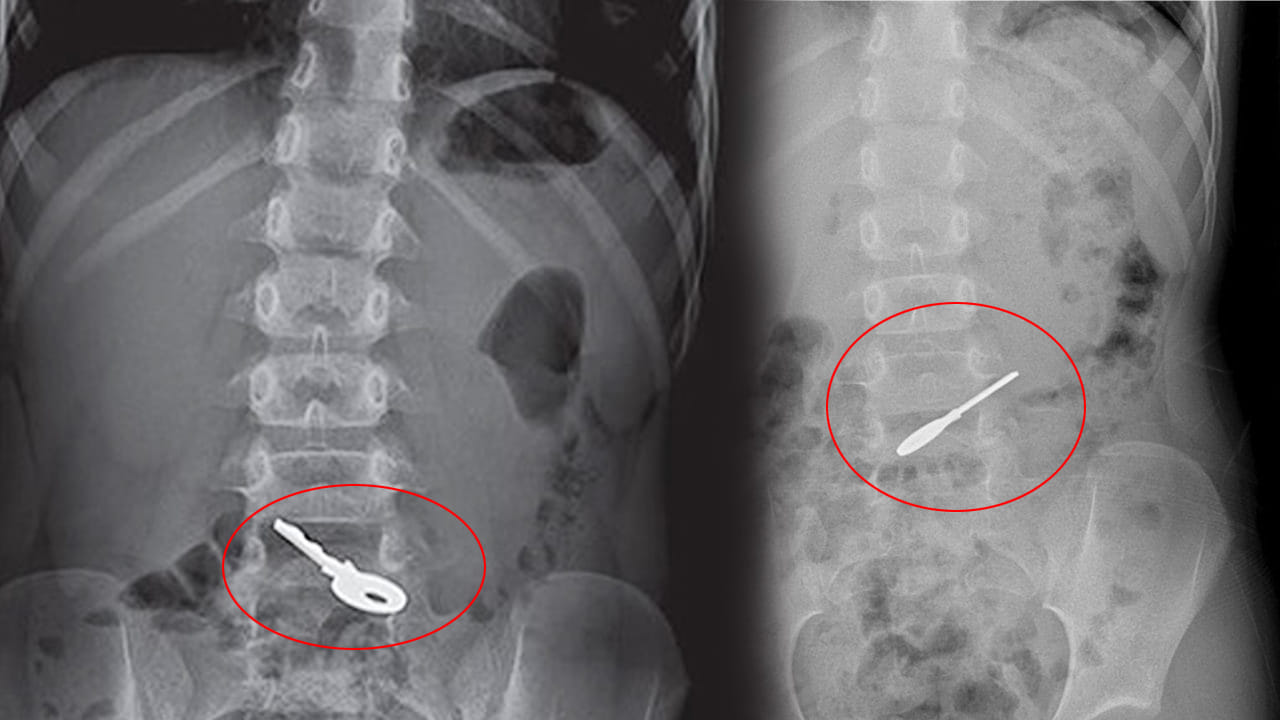

ఇక ఎక్స్రేలో చిన్నారి పొత్తికడుపులో తాళం ఉన్నట్టు డాక్టర్లు గుర్తించారు. ఆ తాళం ద్వారా చిన్నారి శరీరంలో ఎలాంటి సైడ్ ఎఫెక్ట్స్ లేకపోవడం, అలాగే నెగటివ్ లక్షణాలు ఏం ఆమెలో కనిపించకపోవడంతో.. వైద్యులు శస్త్రచికిత్స ద్వారా తాళం తొలగించడానికి ప్రయత్నించకుండా.. చిన్నారిని పర్యవేక్షణలో ఉంచారు.

72 గంటల పాటు చిన్నారిని పర్యవేక్షణలో ఉంచారు. టైం టూ టైం ఎక్స్రేలు తీసి.. ఆ తాళం శరీరం గుండా ఎలా ప్రయాణిస్తోందా అని గమనించారు. చిన్నారిని ఆస్పత్రిలో చేర్చిన 48 గంటల తర్వాత ఆ తాళం పేగుల గుండా వెళ్తున్నట్టు ఎక్స్రేలో గమనించారు డాక్టర్లు. 72 గంటల తర్వాత ఆ చిన్నారికి ఎటువంటి సమస్యలు లేకుండా మలద్వారం గుండా తాళం బయటకు వచ్చేసింది. ఇక్కడ ఆశ్చర్యకరమైన విషయమేమిటంటే.. ఈ ఘటన వల్ల చిన్నారికి ఎటువంటి దుష్ప్రభావాలు కలగలేదు. ఆమెను ఆ తర్వాత కొద్దిరోజులకే డిశ్చార్జ్ చేశారు. ఈక్వెడార్లో ఈ ఘటన జరగ్గా.. ఆ చిన్నారి ఎలాంటి సమస్యలు లేదని వైద్య బృందం స్పష్టం చేసింది.